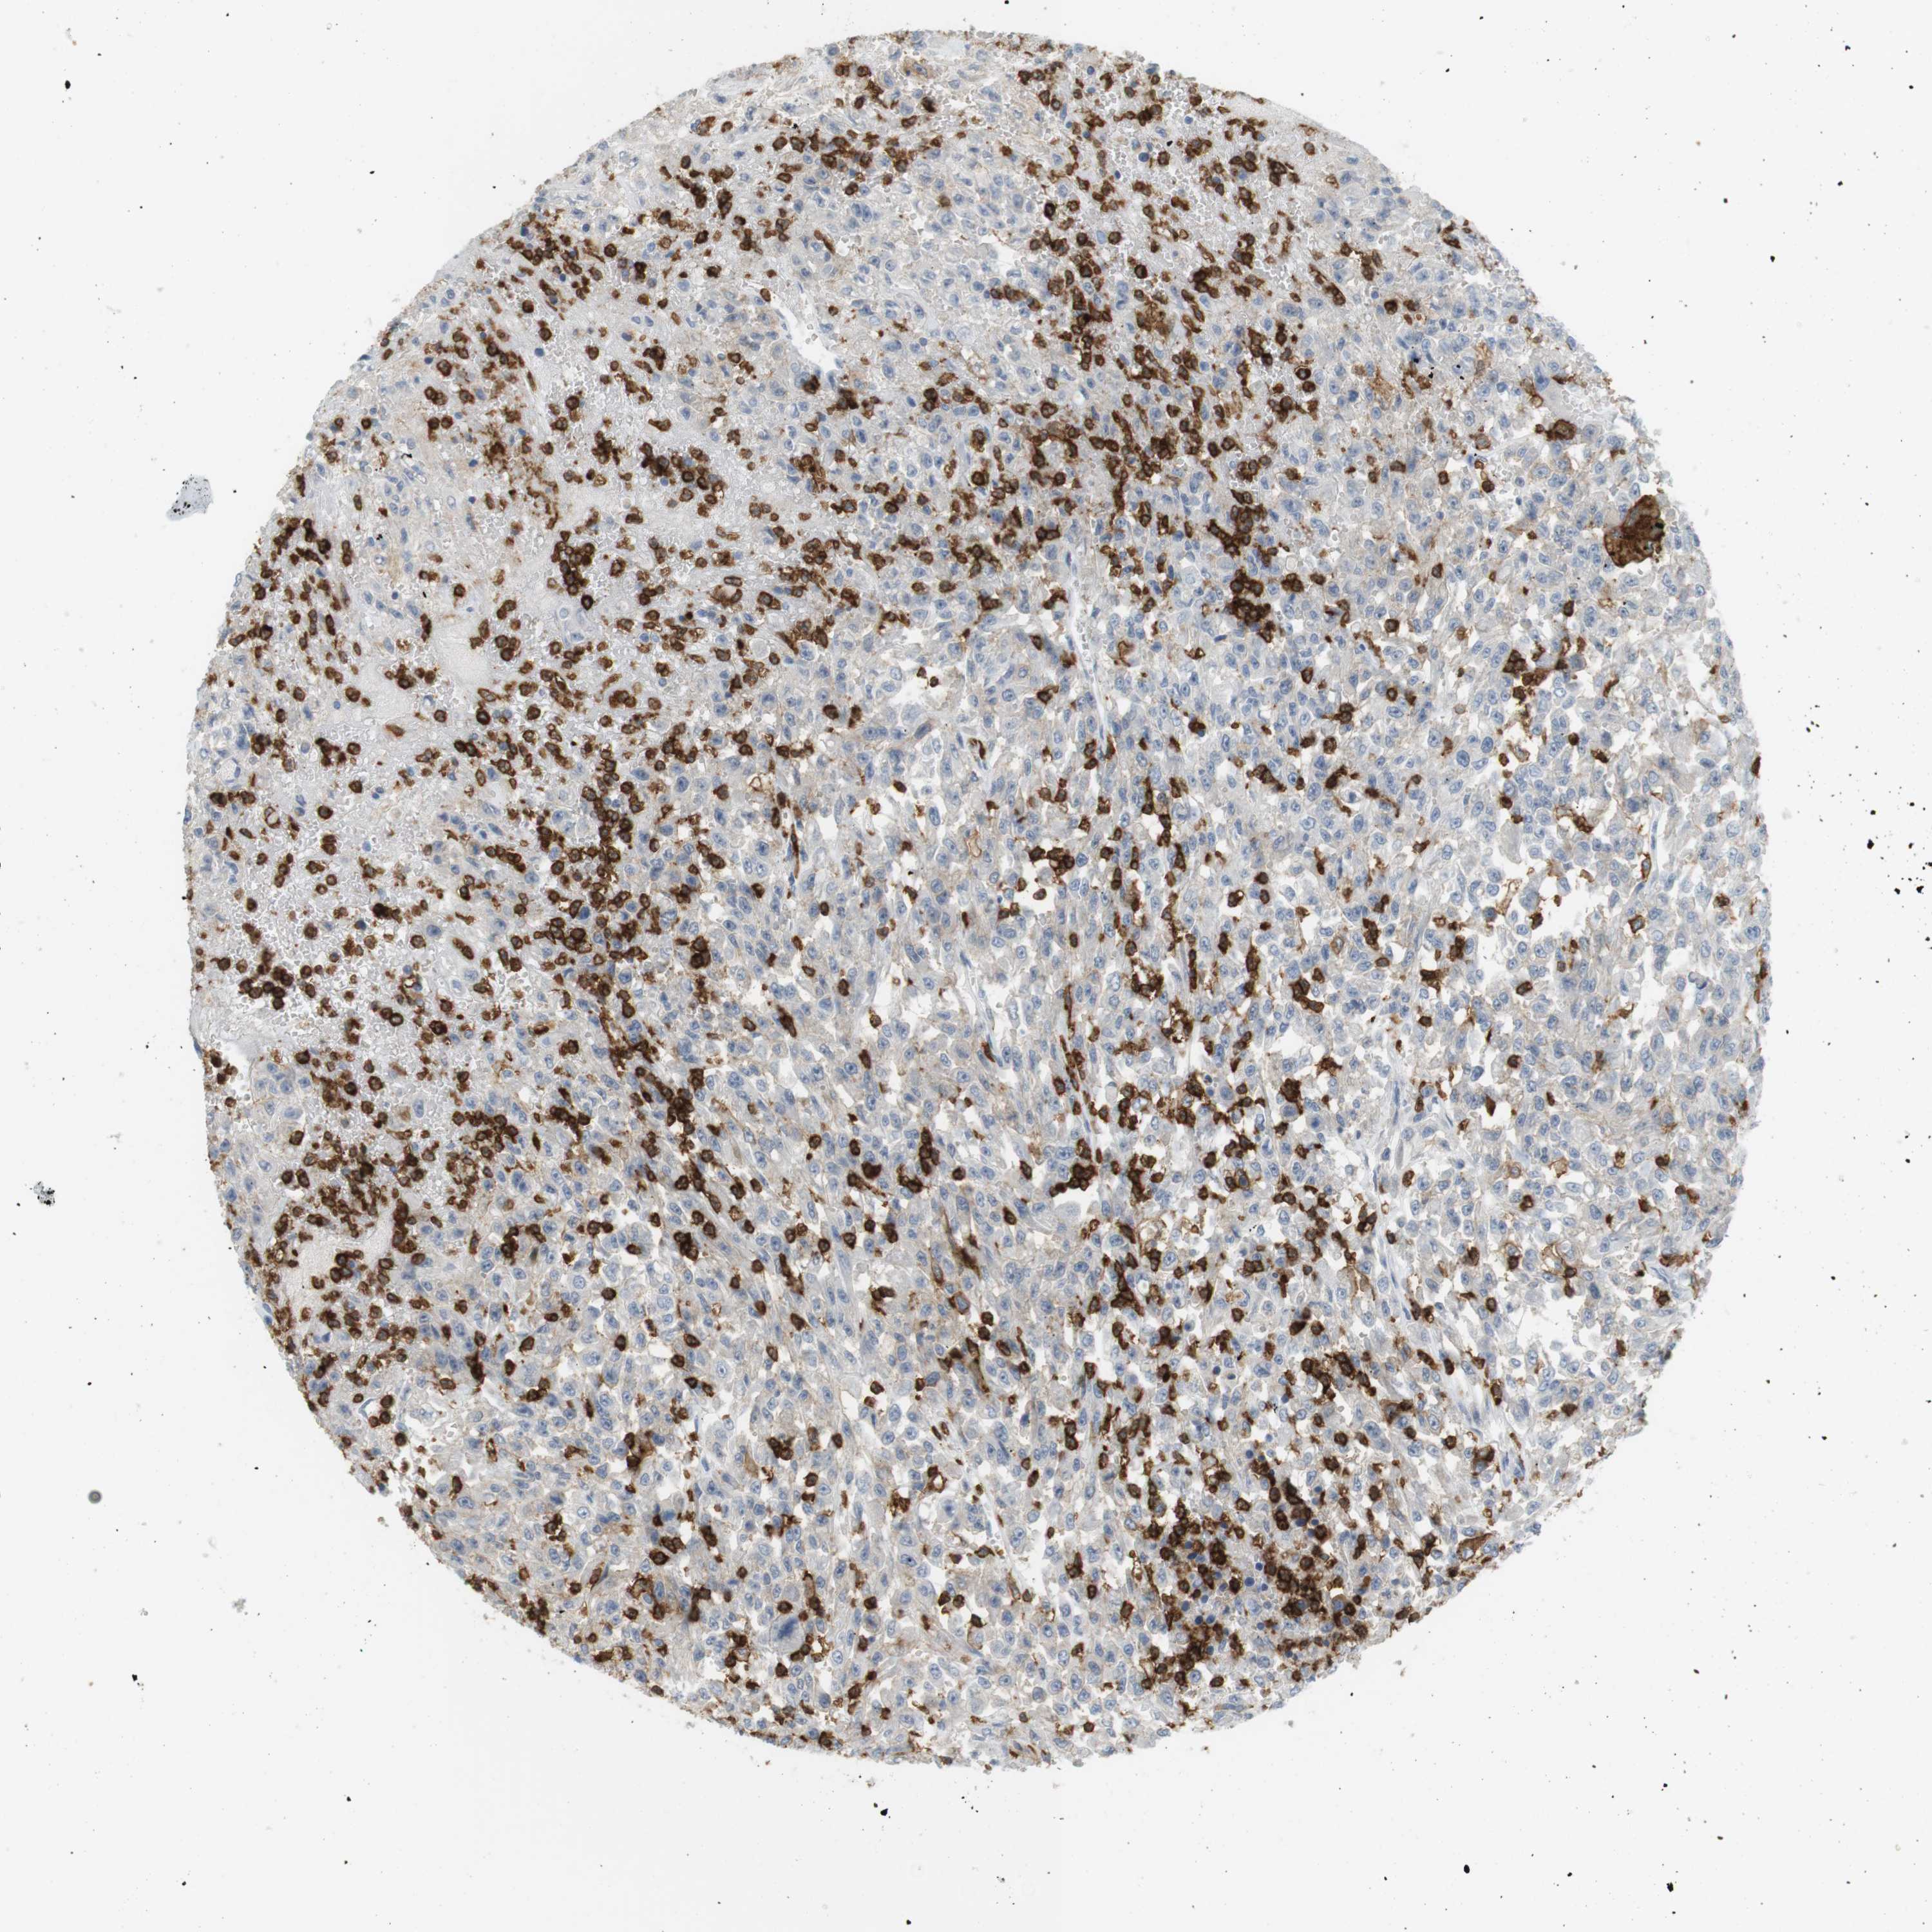

UROTHELIAL CANCER - Protein expressioni

A mouse-over function shows sample information and annotation data. Click on an image to view it in a full screen mode. Samples can be filtered based on level of antibody staining by selecting one or several of the following categories: high, medium, low and not detected. The assay and annotation is described here.

Note that samples used for immunohistochemistry by the Human Protein Atlas do not correspond to samples in the TCGA dataset.

Antibody stainingi

Antibody staining in the annotated cell types in the current human tissue is reported as not detected, low, medium, or high, based on conventional immunohistochemistry profiling in selected tissues. This score is based on the combination of the staining intensity and fraction of stained cells.

Each image is clickable and will lead to virtual microscopy that enables deeper exploration of all samples and also displays staining intensity scores, fraction scores and subcellular localization as well as patient and tissue information for each sample.

Antibody HPA054437

Antibody HPA058511

Antibody CAB002776

Antibody CAB015122

Staining

High

Medium

Low

Not detected

Intensity

Strong

Moderate

Weak

Negative

Quantity

>75%

75%-25%

<25%

None

Location

Nuclear

Cytoplasmic/membranous

Cytoplasmic/membranous,nuclear

Urothelial carcinoma, High grade

Urothelial carcinoma, Low grade

Urothelial carcinoma, NOS